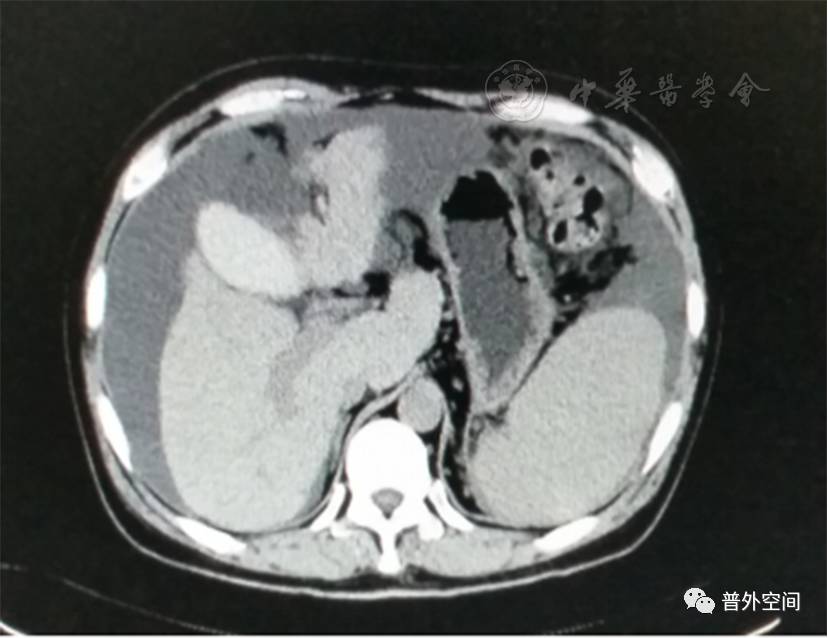

我们将这种方法应用到100多例没有艾滋病病毒感染的一般肝硬化患者身上,结果收到更好的疗效。例如1例男性患者,56岁,失代偿期肝硬化大量腹水合并脐疝(见封四,图1)。CT检查提示肝脏明显萎缩,肝脏体积1 302 ml,大量腹水,脾脏肿大(见封四,图2)。在多家医院就诊后都认为需要做肝移植。我们对患者进行脾切除加脐疝修补,自体骨髓经门静脉输注治疗。手术后3个月,肝功能Child-Pugh分级从C级转成*级A**,手术后1年,肝功能正常,腹部伤口愈合良好(见封四,图3)。CT检查提示肝脏明显增大,体积1 796 ml,腹水基本消失(见封四,图4)。对于肝功能C级的患者手术风险比较高,围手术期输注白蛋白、凝血酶原复合物、纤维蛋白原,改善肝脏功能,手术中经胃网膜右静脉插管埋置骨髓输注设备,输注自体骨髓。随着自体骨髓干细胞在肝内发生复杂的变化,肝硬化组织中的胶原纤维被降解和吸收,肝脏组织的增生和体积增大,肝功能好转,门静脉压力会逐渐降低。但是在手术后1年内,仍然有可能随时发生上消化道出血,需要经胃镜检查,套扎食管黏膜下明显曲张的静脉血管。这样我们做脾脏切除解除脾功能亢进,不做贲门周围血管离断,减少了手术损伤。食管黏膜下静脉曲张用胃镜下套扎治疗。待肝硬化逐渐逆转,食管黏膜下静脉曲张程度将会逐渐减轻。

图2 手术前腹部CT断层照片